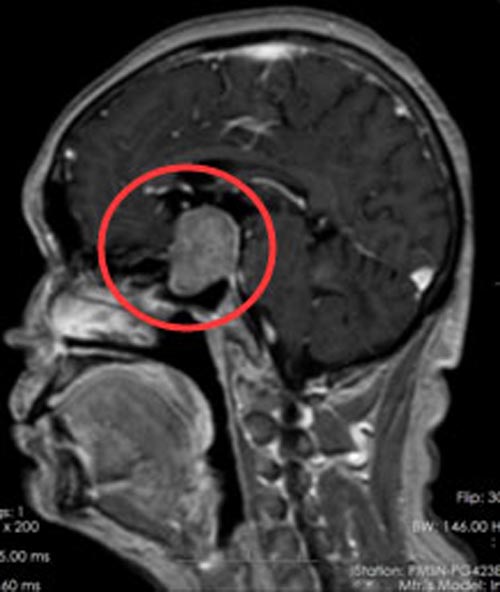

入住广东三九脑科医院垂体瘤诊疗中心,头颅MR提示:鞍区示团块状稍低、高混杂信号影,范围约3.7cm×2.6cm×2.4cm,垂体炳及视交叉显示不清,邻近双侧颈内动脉受压,左侧部分被包绕。